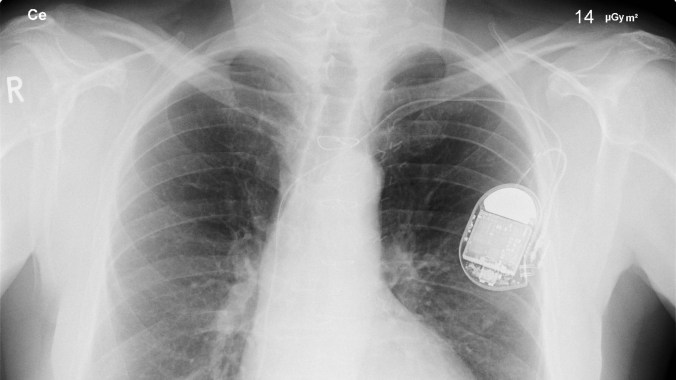

Certain inherited mutations as well as the aging process can foul up this natural pacemaker signal which usually results in slower, erratic heart rates and leads to poor blood circulation. The current remedy for irregular heart rhythm in these cases is the implantation of an artificial electronic pacemaker into the body. But these devices have their drawbacks: they can’t respond to hormone signals received by the heart, the implantation itself carries a risk of infection and the pacemaker’s battery life is limited to about 7 years so replacement surgeries are needed. Also, for children needing artificial pacemakers, there’s no effective way to adjust the device to adapt to a child’s growing heart.

X-Ray of implanted electronic pacemaker (Image: Wikipedia)